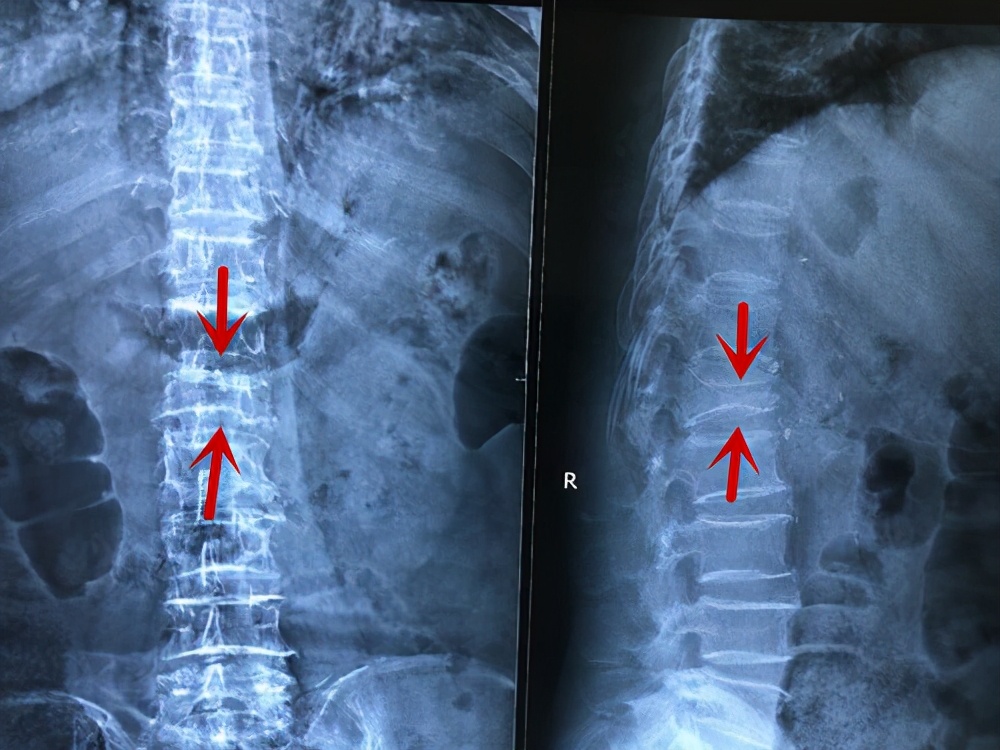

首先是要确诊,X线可以作为初步的检查,判断椎体是否有压缩性改变。

翻身疼深呼吸疼是怎么回事,向左翻身疼是怎么回事